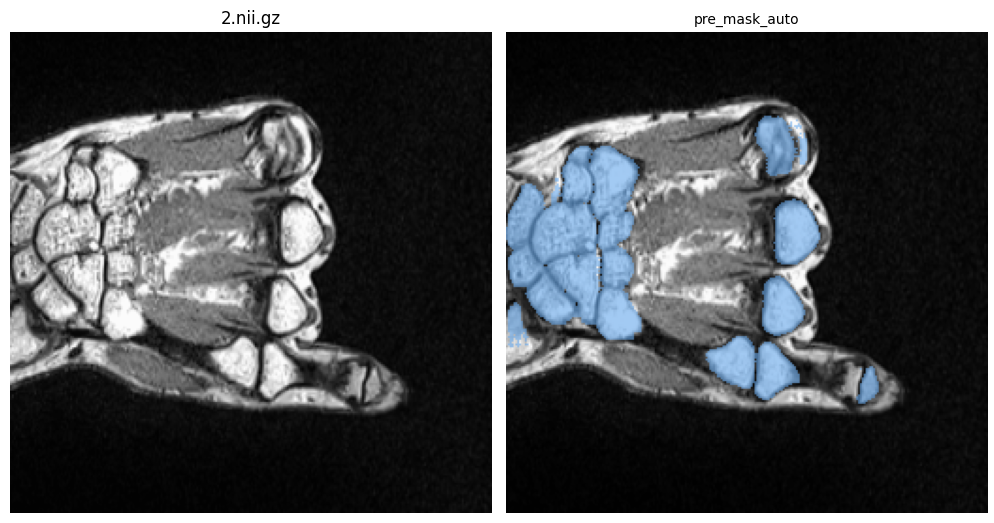

After cloning the repository and downloading the checkpoints to the project folder, you should put your 3D MRI volume in /images, and your ground truth mask in /masks folder if you want to evaluate the segmentation performance of SegmentAnyBone. If you need to segment 3D volume instead of 1 slice you can see the 3D segmentation mask under /predicted_masks after you run predictVolume() or predictAndEvaluateVolume() function. This notebook will guide you to use SegmentAnyBone in a slice-based and volume-based manner thanks to following predictSlice(), evaluateSlicePrediction()_, and predictAndEvaluateVolume() functions:

ori_img, predictedSliceMask, atten_map = predictSlice(

image_name = '2.nii.gz',

lower_percentile = 1,

upper_percentile = 99,

slice_id = 50, # slice number

attention_enabled = True, # if you want to use the depth attention

)